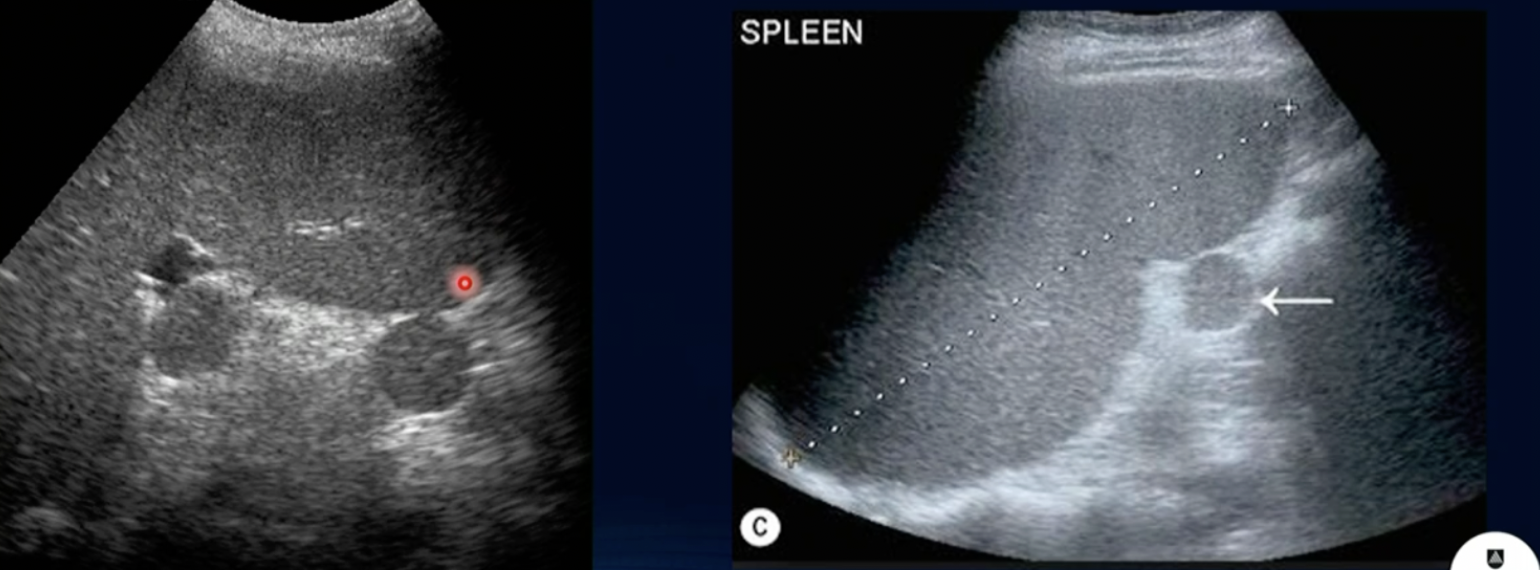

What is this?

Splenuculi

Pathology?

Splenic Calcification (Post. Acous. shadowing + Echogenic appearance)

Path?

Haemangioma of Spleen (no B/F)

Splenic Infarction (Anechoic Region)